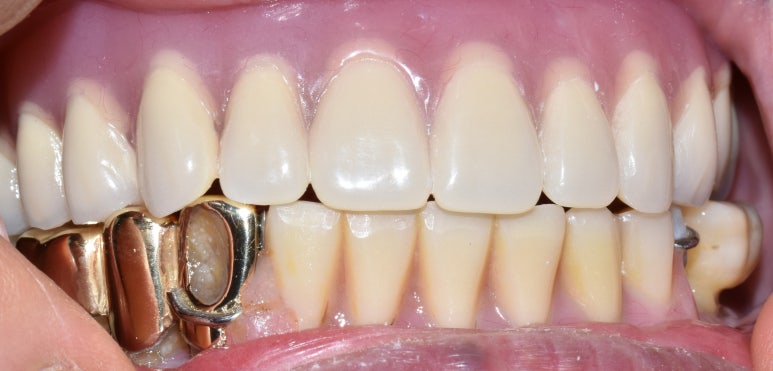

- 상악 전체임플란트, 하악어금니 없는 부분 임플란트

상악 흔들리는 브릿지와 치아 발치 후 상악전체 임플란트

↓

상악 전체 임플란트 후

- 상악 전체임플란트 및 하악 어금니 없는 부위 임플란트